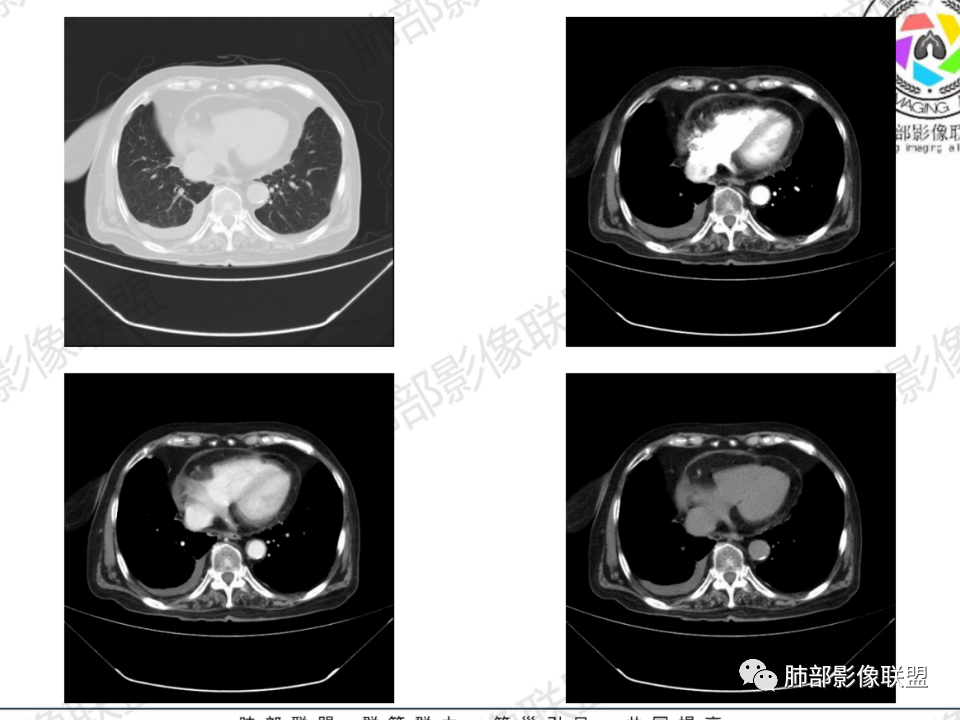

那个人:老年女性,亚急性病程,咳嗽发热。有垂体前叶功能减退,目前激素替代治疗,长期激素,量小,不知道累积量,没有目前激素水平指标。既往有淋巴结结核病史。肿瘤标记物Ca125升高。血沉升高,C反应蛋白轻度异常。影像,右肺上叶靠近肺门团块影,右肺门淋巴结钙化肿大,支气管狭窄,局部增厚,团块影外朝内改变,强化明显,血管破坏不明显,有粘液。和纵隔胸膜分界清楚,周围肺组织有斑片渗出影,右侧胸腔积液,考虑炎性?结核?支气管镜检查除外恶性飞鹰行动:老年患者,影像表现 右肺上叶占位性病变,边界清楚,有分叶征,内见细小钙化,右肺上叶支气管截断,增强病灶不均匀强化,病灶内有条状坏死区(扩张的支气管?),纵膈内未见增大淋巴结,考虑炎性病变,结核可能。一切∮随缘:右肺上叶实性肿块形态不规则,呈三角形,边缘分叶,边界伴有磨玻璃影,近段支气管未见明显显示,可能堵塞,病变平扫密度均匀,增强后可见低密度坏死无强化,周围略强化,右肺下叶散在结节。心包积液,及右侧胸腔积液,临床:有低热,低蛋白血症,肿瘤标记物高,考虑恶性:腺癌,神经内分泌癌(强化偏弱了),淋巴瘤,鉴别:结核红星:老年女性患者右肺上叶,肺门上区 分叶状肿块 ,右肺上叶支气管显示不清,增强扫描肿块,中等程度强化可见小斑片状坏死区,病灶内部可见斑点状钙化灶,病灶周围可见斑片状及小斑点状影,纵膈淋巴结增大,其他区域,胸膜下可见斑点状钙化。考虑肉芽肿性病变,结核的可能性大。老年患者最排除肿瘤性病变腺癌。土娃:右上肺不规则肿块影,边缘分叶,边界磨玻璃影欠清,病灶分叉状,内见点状钙化影及坏死灶,支气管堵塞,病灶增强强化不明显。考虑瘤样结核,鉴别淋巴瘤。张小兵:老年女性,亚急性病程,右肺上叶见不规则肿块,边缘平直凹陷为主,周围GGO边界不清,内见点状钙化及坏死灶,增强持续性渐进强化,右侧少量胸腔积液,双肺门及纵隔肿大淋巴结伴钙化,综合考虑慢性炎症。saf:老年患者,影像表现 右肺上叶占位性病变,边界清楚,有分叶征,增强病灶明显不均匀强化,纵膈内未见增大淋巴结,考虑炎性病变,结核可能。小兜:老年女性,咳嗽喘息一月,发热三天,肿瘤标志物升高,长期激素替代治疗。CT示右肺上叶近肺门不规则实变影,周围伴磨玻璃影,增强持续性渐进强化,内部血管破坏不厉害,内部可见多发条形低密度灶,右侧胸腔可见少量积液,双肺门及纵隔可见钙化淋巴结,考虑为炎性病变,结核可能玫:女,79咳嗽,喘息一月,发热三天入院,右肺上叶不规则形软组织密度肿块影,边界清晰,边缘见分叶及细短毛刺,病灶内见点状钙化影及稍低密度区,病灶边缘呈磨玻璃样改变,增强扫描,病灶呈不均匀性强化,考虑炎性病变,鉴别鳞癌。大雄:老年女性,既往诊断淋巴结结核,提示已治愈,近2年服用激素,诱导结核复燃→发热;纵隔肺门淋巴结肿大钙化,压迫支气管,右肺上中下叶支气管均狭窄→喘息咳嗽;尖段支气管受累闭塞→肺不张、支气管粘液栓;累及胸膜,结核性胸膜炎并胸水→右侧胸痛;实验室,血沉快,CA125高,低蛋白,符合;下一步,支气管镜尖段支气管刷检抗酸染色周太狼:老年女性,亚急性病程,肿瘤标志物升高。CT示右肺上叶尖段不规则肿块影,有分叶、收缩,周围伴磨玻璃影,增强渐进强化,内部可见多发条形低密度灶,右侧胸腔及心包少量积液,纵隔内淋巴结稍增大。倾向于恶性病变,肺癌伴阻塞性炎变可能。丽:老年女性,右肺上叶不规则软组织肿块,边缘清晰,内密度不均,可见点状钙化及粘液栓,周围可见片状高密度影,增强后均匀强化,内多发低密度,纵膈多发钙化淋巴结,考虑结核可能大,建议结合支气管镜检查除外肿瘤宇宙:右胸廓缩小,右肺上叶团块影及不张,平直边,周围磨玻璃影,纤细胸膜牵拉,上叶尖段支气管堵塞,明显延迟强化,可见支气管粘液栓,两肺门钙化淋巴结,右侧胸水,考性炎性肉芽肿,鉴别腺癌王秀仙:右肺上叶肺门区肿块,上叶支气管开口阻塞,形态不规则,密度不均,内可见支气管粘液栓及多发小灶性坏死,周围磨玻璃影边缘模糊,渐进强化,右侧胸腔积液、胸膜钙化,考虑炎性肉芽肿性病变,慢性炎症。鉴别鳞癌,结核。刘丹:老年女性,右肺上叶肿块伴钙化,右肺上叶支气管截断,增强后均匀强化,周边可见点片状模糊影,右侧胸腔积液,右肺门淋巴结增大,考虑占位并阻塞性炎症,肿瘤?结核?建议纤支镜检查。小飞:右肺上叶纵隔旁软组织肿块,边缘深分叶、长毛刺及毛刷样短毛刺,边缘磨玻璃影,磨玻璃边界模糊,支气管截断,平扫密度不均,可见点状钙化,增强不均匀明显强化,心影增大,心包积液,右侧胸腔积液,考虑恶性肿瘤,腺癌?秦化君:右肺上叶不规则分叶软组织密度肿块,边缘清晰,胸膜牵拉,周围花花草草,上叶尖段支气管阻塞,内可见点状钙化,增强后密度不均可见支气管粘液栓及坏死区,内见血管分枝。中间段及中叶,下叶支气管狭窄,壁见钙化。右肺门淋巴结肿大,右侧胸腔积液,心包粘连肥厚。考虑1右上肺恶性病变,鳞癌?2右肺多叶段支气管狭窄,考虑支气管内膜结核?3胸腔积液及肺门淋巴结肿大,转移?风儿:老年女性,右肺上叶肿块,形态不规则,外围大内带小,边缘分叶膨隆平直及毛糙,密度不均,内见支气管粘液栓及多发小灶性坏死,坏死边缘清晰 ,渐进强化,上叶尖段支气管阻塞,叶支气管壁有局限性增厚,邻近胸膜腔微积液;纵隔及双肺门淋巴结肿大,部分钙化,右侧胸腔积液、心包积液、胸膜钙化,考虑炎性,肉芽肿性结核可能性大。鉴别鳞癌,女性及血供均不支持;腺癌,坏死边界太清晰。流心明智:老年女性,79岁,咳嗽、气短1月,发热3天。胸CT:右肺上叶见不规则肿块,边缘有膨隆、有平直凹陷,周围GGO边界不清,病灶内见点状钙化、粘液栓,尖段支气管未见,增强持续性渐进强化,右侧少量胸腔积液,双肺门及纵隔肿大淋巴结伴钙化,肺动脉增粗。考虑:右上叶尖段堵塞并慢性炎症,支气管TB并结石?鉴别Ca

临床信息:老年女性,亚急性病程,咳嗽发热。有激素使用史。既往有淋巴结结核病史。肿瘤标记物Ca125升高。血沉升高,C反应蛋白轻度异常。 影像所见:右侧胸廓相对狭小,右肺上叶不规则团块影贴附纵隔旁,轻度分叶,整体密度较均匀,偶见钙点。

相应上叶尖端及前段支气管开口未能追踪(阻塞),开口处见钙化。病灶渐进性强化,并衬托出较完整尖段及前段含液支气管影。支气管开口区域未见异常高密度强化(如类癌等)及相对乏血供区(如鳞癌)。病灶区未见液化坏死。右上纵隔及胸廓入口区未见病灶胸膜外突破(栽赃)。

右肺上叶后段等区域散在片状影,边界不清(提示渗出性病灶)。

纵隔及双肺门见钙化淋巴结。心包积液,右侧胸腔积液(提示存在活动新病灶)。双侧胸膜下见多发斑点状钙化,胸廓变形(提示存在结核基础病变可能)。 诊断意见:综上,右肺上叶块状影更符合继发性肺结核。 最后小结:既往诊断淋巴结结核,提示已治愈。近2年服用激素,可疑诱导结核复燃,也可引起发热。纵隔肺门淋巴结肿大钙化,压迫支气管,右肺上中下叶支气管均狭窄,所以引起喘息咳嗽。尖段支气管受累闭塞,导致肺不张、支气管粘液栓,出现条状无强化区。病变累及胸膜,导致结核性胸膜炎并胸水,引起右侧胸痛。实验室检查血沉快,CA125高,低蛋白,均符合结核。下一步,建议支气管镜尖段支气管刷检并抗酸染色。(本段摘自於雄老师精彩发言)